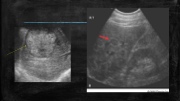

Page 18 - SONO 260 Patologías Hígado